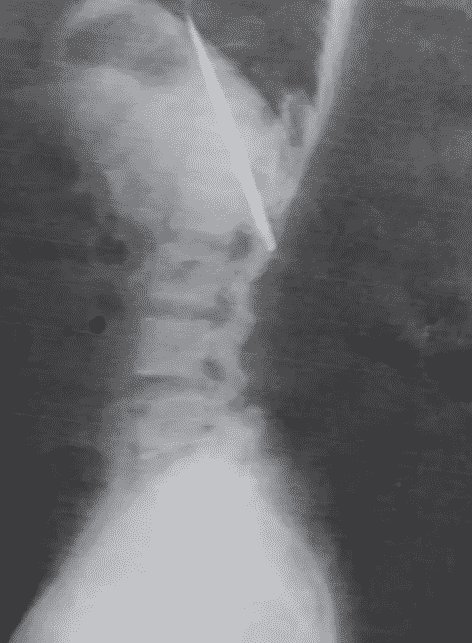

- He was later shocked to find out that he had a 4-inch knife inside his body.

A 25-year-old man from the Philippines made a surprising discovery after getting an X-ray just recently: he had a 4-inch knife lodged in his chest!

Fast forward to the present, Kent had to undergo an X-ray as a requirement for a job and he discovered that the weapon is still inside his body – and is, in fact, just several inches away from his lungs.